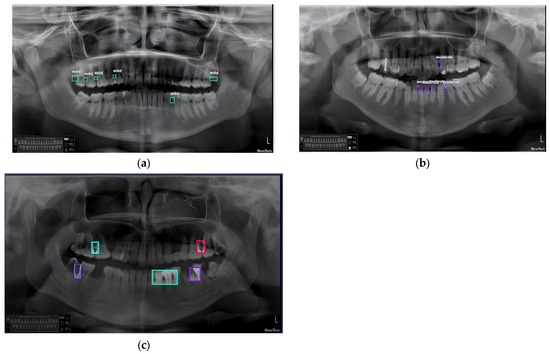

3.3. Results of the Secondary Model (YOLOv8)

4.2.2. The Secondary Model (YOLOv8)